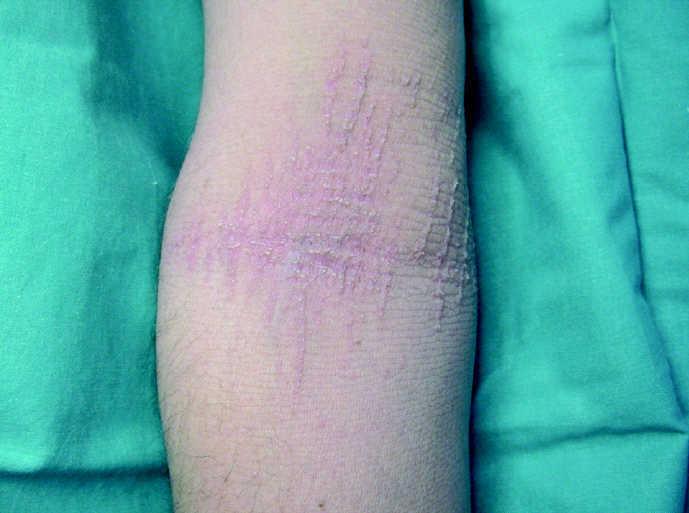

En la exploración física se observaba una queratodermia palmoplantar difusa, con estrechamientos constrictivos anulares alrededor de los dedos de las manos y de los pies (tipo pseudoainhum), pero más marcados en el quinto dedo (figs. 1 y 2). Además se apreciaba una dermatosis ictiosiforme generalizada, sobre todo en extremidades, con escamas blanquecinas y de evidente rugosidad al tacto (fig. 3). En regiones poplíteas y fosas antecubitales se formaban grandes placas queratósicas, a expensas de elementos puntiformes hiperqueratósicos, que adoptaban una distribución lineal (fig. 4). No observamos alteraciones en pelo, uñas o dientes. El estudio oftalmológico y otorrinolaringológico no evidenció alteraciones reseñables.

Fig. 4.--En las fosas antecubitales se observan placas hiperqueratósicas que adoptan una distribución lineal.